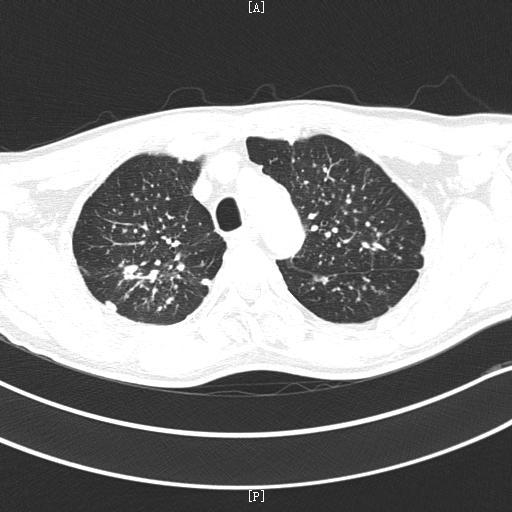

另外,生气的人更容易导致免疫功能低下,免疫功能受损,容易引起肺结节。那么中医如何解决这种“气怒”的肺结节人群呢?分享几个案例。案例1:马先生,65岁,吸烟30多年。2020年7月,因胸闷、胸痛、憋气等症状到医院就诊。CT检查后显示双肺多发结节。左肺下叶胸膜下有较大的实性结节,直径约6 mm,未给予其他治疗。

2019年初,一个很冷的早晨,她感冒起床,咳嗽,痰中带血。在家人陪同下,到中国人民解放军总医院海南分院复查。CT结果显示左肺上叶纵隔及胸膜下见斑片,边界不清。双肺下叶增加一个直径约7mm的磨玻璃小结节,边界清晰。这次陈女士慌了,担心是肺癌。她想马上手术切除肺结节,但很多医生都拒绝了。医生说很可能是良性的,建议随访。

随着CT检查和体检的普及,很多朋友都发现肺部有结节。我们所说的肺结节是指直径小于3厘米的圆形或类圆形结节阴影,大于3厘米的称为肿块。肺部的结节小于1 cm就叫小结节,小于< 0.5cm就叫微小结节,发现肺部结节就要找专科医生帮忙分析原因,因为这些结节有的是炎症引起的,有的是良性结节,可能多年不变,有的可能是恶性肿瘤的早期萌芽。

双肺多发毛玻璃结节是一种常见的肺部疾病,由多种原因引起,损害了患者的肺部健康,给患者带来困扰,引起咳嗽症状。朋友们一定要警惕这种疾病的发生,一旦发生需要积极治疗,充分了解这种疾病的治疗措施。大多数肺部有玻璃结节的患者是通过体检发现的,没有任何症状。这种肺部的小结节和体表的肿瘤不一样。当胸膜未受累时,由于缺乏相应的感觉神经分布,这些结节一般无症状。